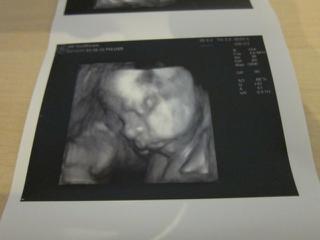

bolo to uzasne, 😵 fakt to stalo za to, sestricka najprv vsetko pomerala, skontrolovala, babo je v poriadku a definitivne sa potvrdilo ze to bude nase vytuzene dievcatko, 😵 podla sestricky je to iste na 1000%. 🙂

Babo sa nenechalo rusit a cele sono prespinkalo, (ani sa necudujem, mali sme rusnu noc, chytila ma choroba tak so mnou ponocovala, 😅 ),

na videu je sice stale kludnucka a len sem tam sa pohmyri ale aspon sa lepsie dalo zachytit foto, aj ked si davala stale rucicku pred tvaricku a niekedy tam ta rucicka zavadzala. 😉

Ale aj tak som maximalne spokojna, stale sa neviem vynadivat na bambulku, 😵 je uzasna, meria 37 cm a vazi 1150 g, zodpoveda 27tt, (dnes zacinam 28 tt tak mi to sedi.)

Kuk na foto a dufam ze pridas aj ty. 🙂

Ta prva foto je trochu rozmazana nozicka a foto pod nou dokaz kavoveho zrnka, 😉 na dvd je to lepsie vidiet, tam je to z roznych uhlov. 😉